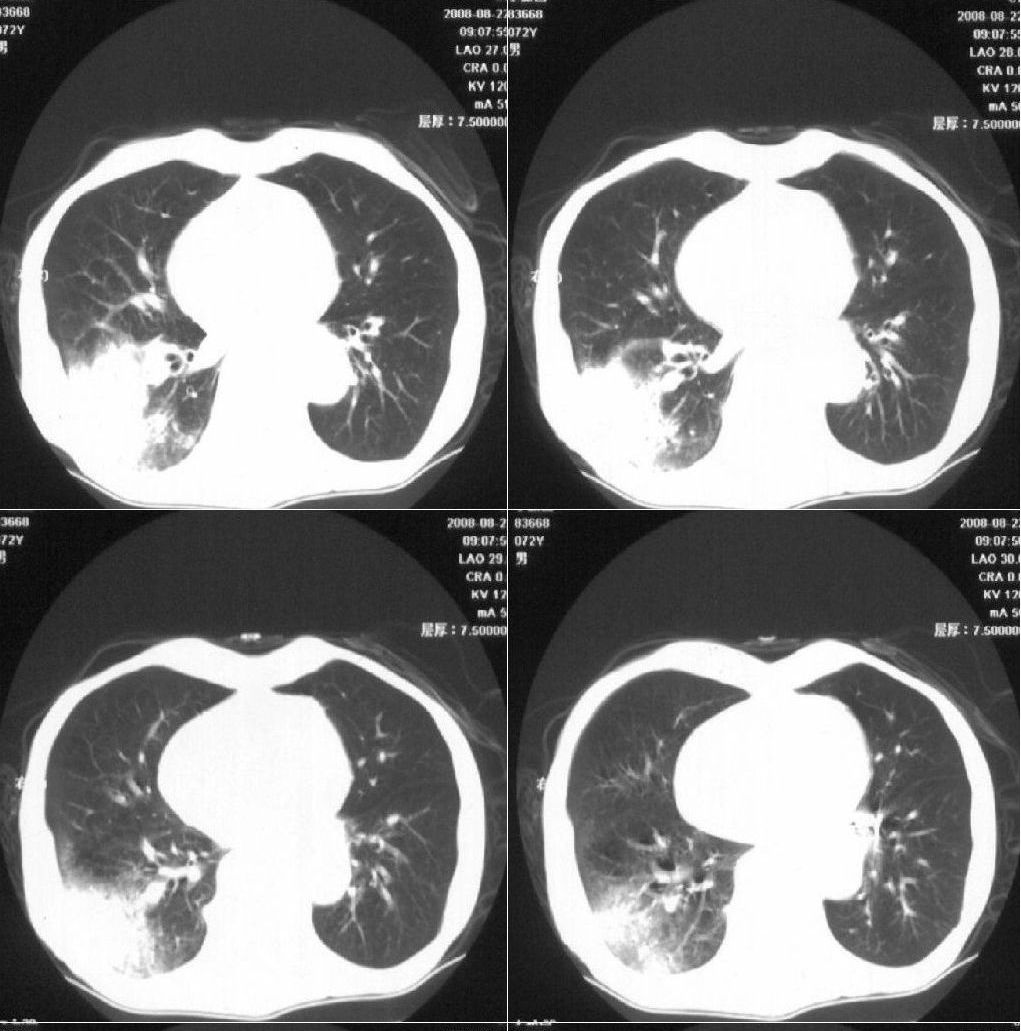

标题: CT15789:男性,72岁。食管癌术后14年。 [打印本页]

标题: CT15789:男性,72岁。食管癌术后14年。

痰培养:见葡萄球菌,霉菌少量生长。(此片系外院所作,仅提供了增强后的ct值为100hu,中心的坏死部分无强化,患者现在身体状况欠佳,为恶液质状态)

考虑右肺下叶感染性病变(肺脓肿?);建议抗炎治疗后复查。

考虑右下肺慢性感染性病变

符合机遇性感染,真菌可能性大。